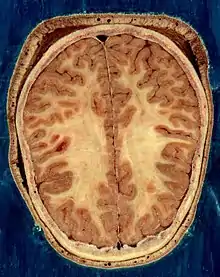

The human brain, obtained after an autopsy | |

Human brain and skull | |